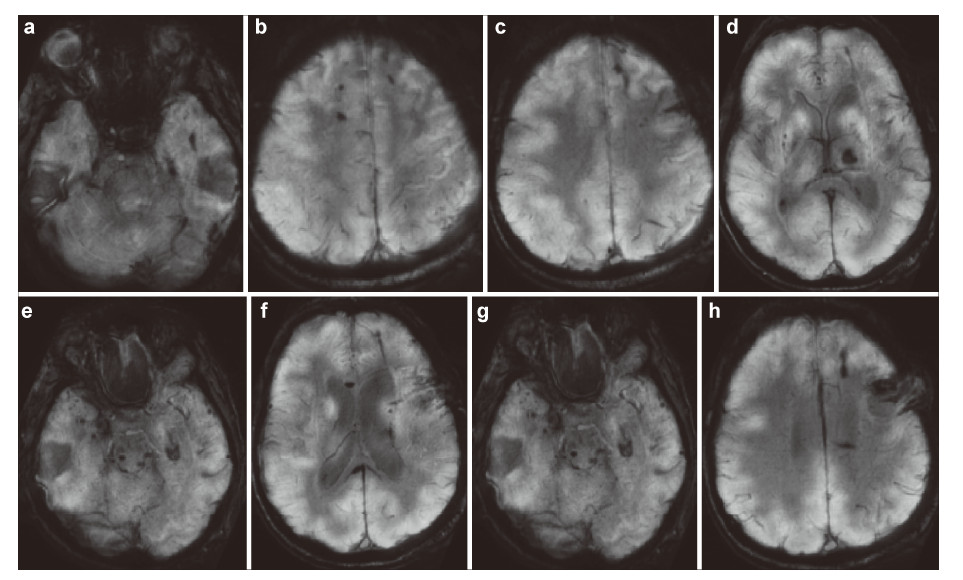

The data of the analysis of metabolic changes in different areas of the brain/spinal cord can be received from PET. Fusion of the PET images with the CT permits accurate coupling of the evidence of metabolomic disorder in the site of injury and its localization in organs and tissues. Therefore,the technology of the fused PET/CT opens new perspectives in the diagnostics of morphofunctional changes and their location in the anatomical formation of the brain. We can receive the data about magnetization of NT as a functional characteristic of the NT damage using magneto-encephalography (MEG). The data of threedimensional mapping of EEG provide us the evidence of the location of bioelectric activity of the brain cortex.

Program fusion of these data in the tables of bio information mapping of the brain with the data of MRI and CT gives us integral characteristic and maximally verified biological information of the personalized data that can be used by contemporary IT‐technologies and methods of mathematical modeling. Hence,these contemporary data of the imaging of the human brain help plan our restorative efforts in the neuroengineering, determine the main directions and information levels of the reconstruction of the brain and spinal cord and to evaluate the scope of requisite biomaterials and instruments. The specialized software for multilevel fusion (multi‐fusion) of the data of MRI,CT,PET,EEG mapping and MEG will produce a table of the parameters of different brain areas,so that it is possible to compare it with the table of the norm and to detect the injuries and functional disorders that have been missed by the physician during the visual analysis.